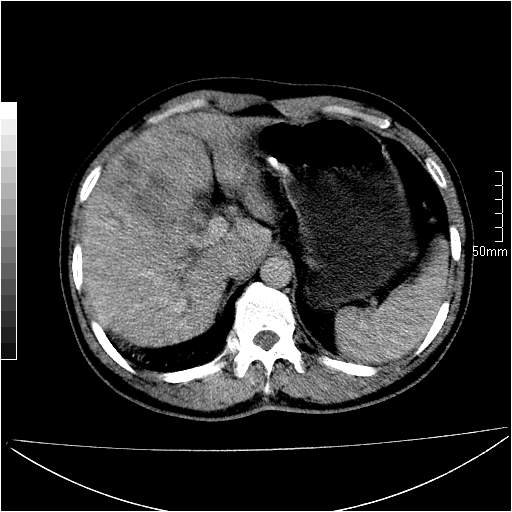

男性,54岁,皮肤黄染,搔痒一周余.b超示肝左叶回声异常.初步诊断1胆总管下段结石2胆囊结石伴慢性胆囊炎请各位战友帮忙看一下肝脏多发低密度如何解释恰当.增强效果不是很好.请大家见谅.

既然做了增强,为什么光提供延时期片子,肝动静脉期肝右叶前下段病灶增强如何?另外胆囊壁增厚,欠规整,内密度不均,与肝右叶病灶分界不清,增强表现怎样?肝内胆管轻度扩张,胆总管扩张,但未见明显结石影,也应提供增强早期图像才好鉴别扩张原因。片子较清,但不够完整,暂考虑1.胆囊癌肝局部浸润,或肝癌胆囊侵犯,2.胆总管下端或胰头钩突部占位。总之本人看不明白,请高手画图指示,先谢了!

由于胆囊窝内结构显示不清,肝脏病灶又邻近胆囊窝首先考虑胆囊癌肝受侵犯。而后因肝脏病灶强化有渐进改变,且相邻胆管扩张,故考虑肝胆管细胞癌待排。

左肝胆管细胞癌。

胆总管下端结石。